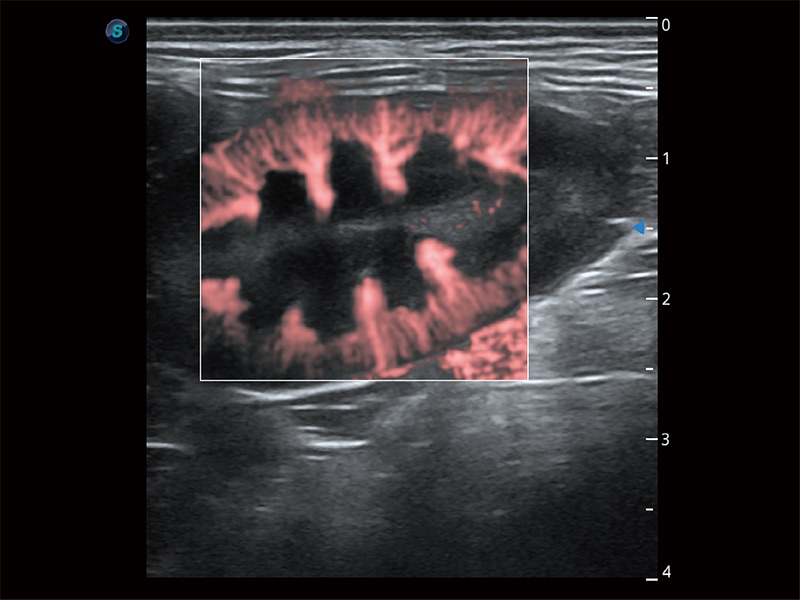

非线性融合造影成像充分利用谐波和基波信号,为难以观察的血流进行增强显像。可用于线阵、凸阵、微凸阵、相控阵探头。

在传统二维血流成像的基础上,呈现血流的立体感,具有动感的生命力之美。即便是微小的血管也能轻松应对,提高了血流的视觉敏感性。